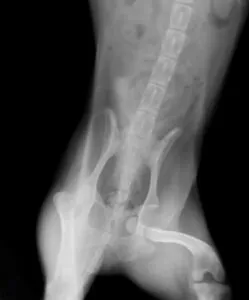

レントゲン撮影をして左股関節の脱臼を認めました。脱臼して時間も経過していなかったため、まずは手術ではなく鎮静下での非観血的整復を試みました。

無事整復できましたが、再脱臼の可能性があるためバンデージ固定による2週間の運動制限を行いました。関節炎改善を促す注射カルトロフェンを週に1回、1か月かけて4回予定しました。